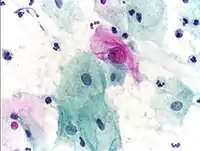

Micrograph of a normal pap smear

Micrograph of a Pap test showing a low-grade intraepithelial lesion (LSIL) and benign endocervical mucosa. Pap stain.

Micrograph of a Pap test showing trichomoniasis. Trichomonas organism seen in the upper right. Pap stain.

Endocervical adenocarcinoma on a pap test.

Candida organisms on a pap test.

Viral cytopathic effect consistent with herpes simplex virus on a pap test.

Normal squamous epithelial cells in premenopausal women

Atrophic squamous cells in postmenopausal women

Normal endocervical cells should be present into the slide, as a proof of a good quality sampling

The cytoplasms of squamous epithelial cells melted out; many Döderlein bacilli can be seen.

Infestation by Trichomonas vaginalis

An obviously atypical cell can be seen